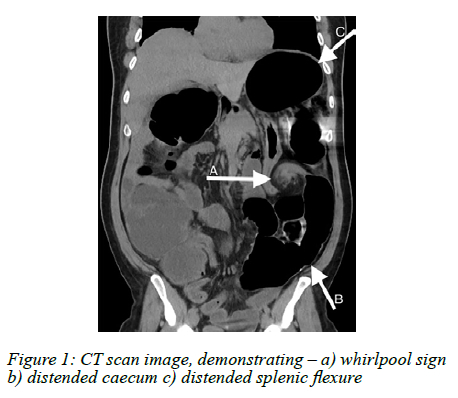

An abdominal radiograph demonstrated markedly distended large and distal small bowel loops with an associated 'coffee bean' sign, indicating large bowel obstruction. An abdominal computed tomography (CT) scan showed a classic 'whirlpool sign' of the mesentery in the left flank with a severely distended colon - caecum, through to splenic flexure (Figure 1). Distal colonic volvulus was considered.